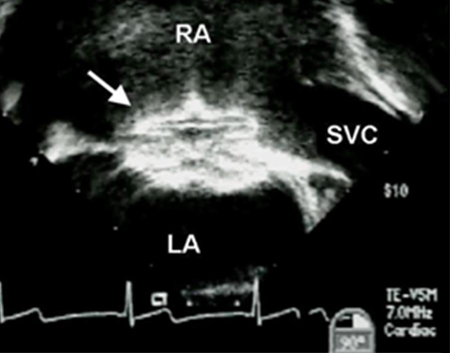

Imagen de ecocardiografía transesofágica de un dispositivo oclusor de comunicación interauricular (CIA) (flecha). (AD) aurícula derecha; (AI) aurícula izquierda; (VCS) vena cava superior